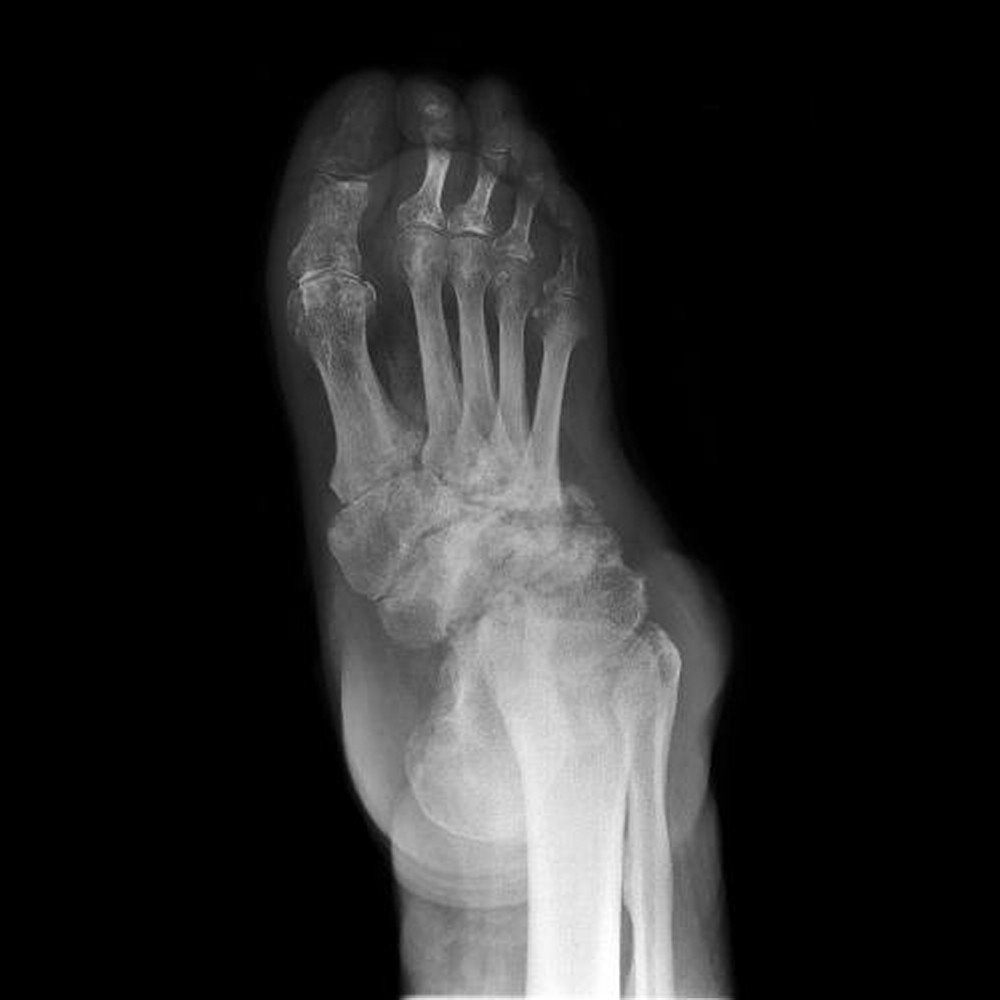

- X-quang: Giúp phát hiện các tổn thương xương và biến dạng khớp.

Chẩn đoán bệnh khớp thần kinh nên được xem xét ở bệnh nhân có rối loạn thần kinh trước đó, xuất hiện tổn thương hủy khớp nhưng không đau tương xứng, thường là vài năm sau bệnh lý thần kinh. Nếu nghi ngờ bệnh lý khớp thần kinh, nên chụp X-quang. Chẩn đoán bằng những bất thường điển hình trên phim X-quang ở bệnh nhân có bệnh nguy cơ và các triệu chứng cơ năng và thực thể điển hình.

X-quang bất thường ở bệnh khớp thần kinh sớm thường tương tự như ở thoái hóa khớp. Các dấu hiệu chính là:

- Mảnh xương

- Phá hủy xương

- Tạo xương mới

- Mất khe khớp

Có thể có tràn dịch khớp và lỏng lẻo khớp. Sau đó, xương bị biến dạng, và các xương mới tạo ở gần vỏ, bắt đầu từ trong bao khớp và thường phát triển theo trục, đặc biệt là trong xương dài. Hiếm khi, sự calci hóa và tạo xương xảy ra trong các mô mềm. Các gai xương có kích thước lớn, kỳ quái có thể có mặt ở rìa hoặc trong các khớp. Những gai xương lớn, cong (mỏ vẹt) thường phát triển ở cột sống khi không có bệnh lý cột sống trên lâm sàng.